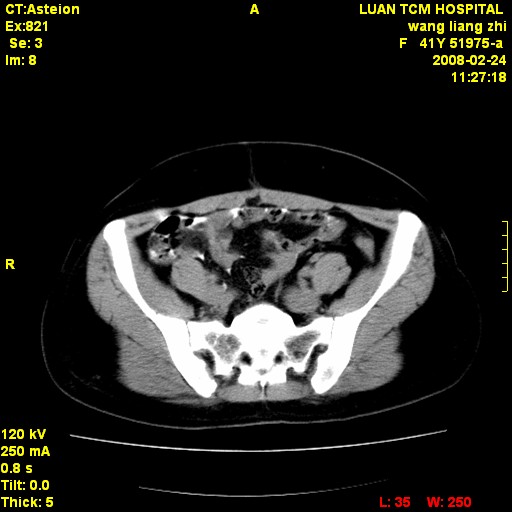

以下是引用dyqct在2009-8-23 16:17:00的发言:[br]考虑:1、造影剂进入腹腔、结肠旁沟、肝周;[br] 2、子宫明显增大(腺肌增生症?);[br] 3、膀胱显影是由于造影剂吸收后经肾分泌进入膀胱的;[br] 4、建议mri检查子宫。